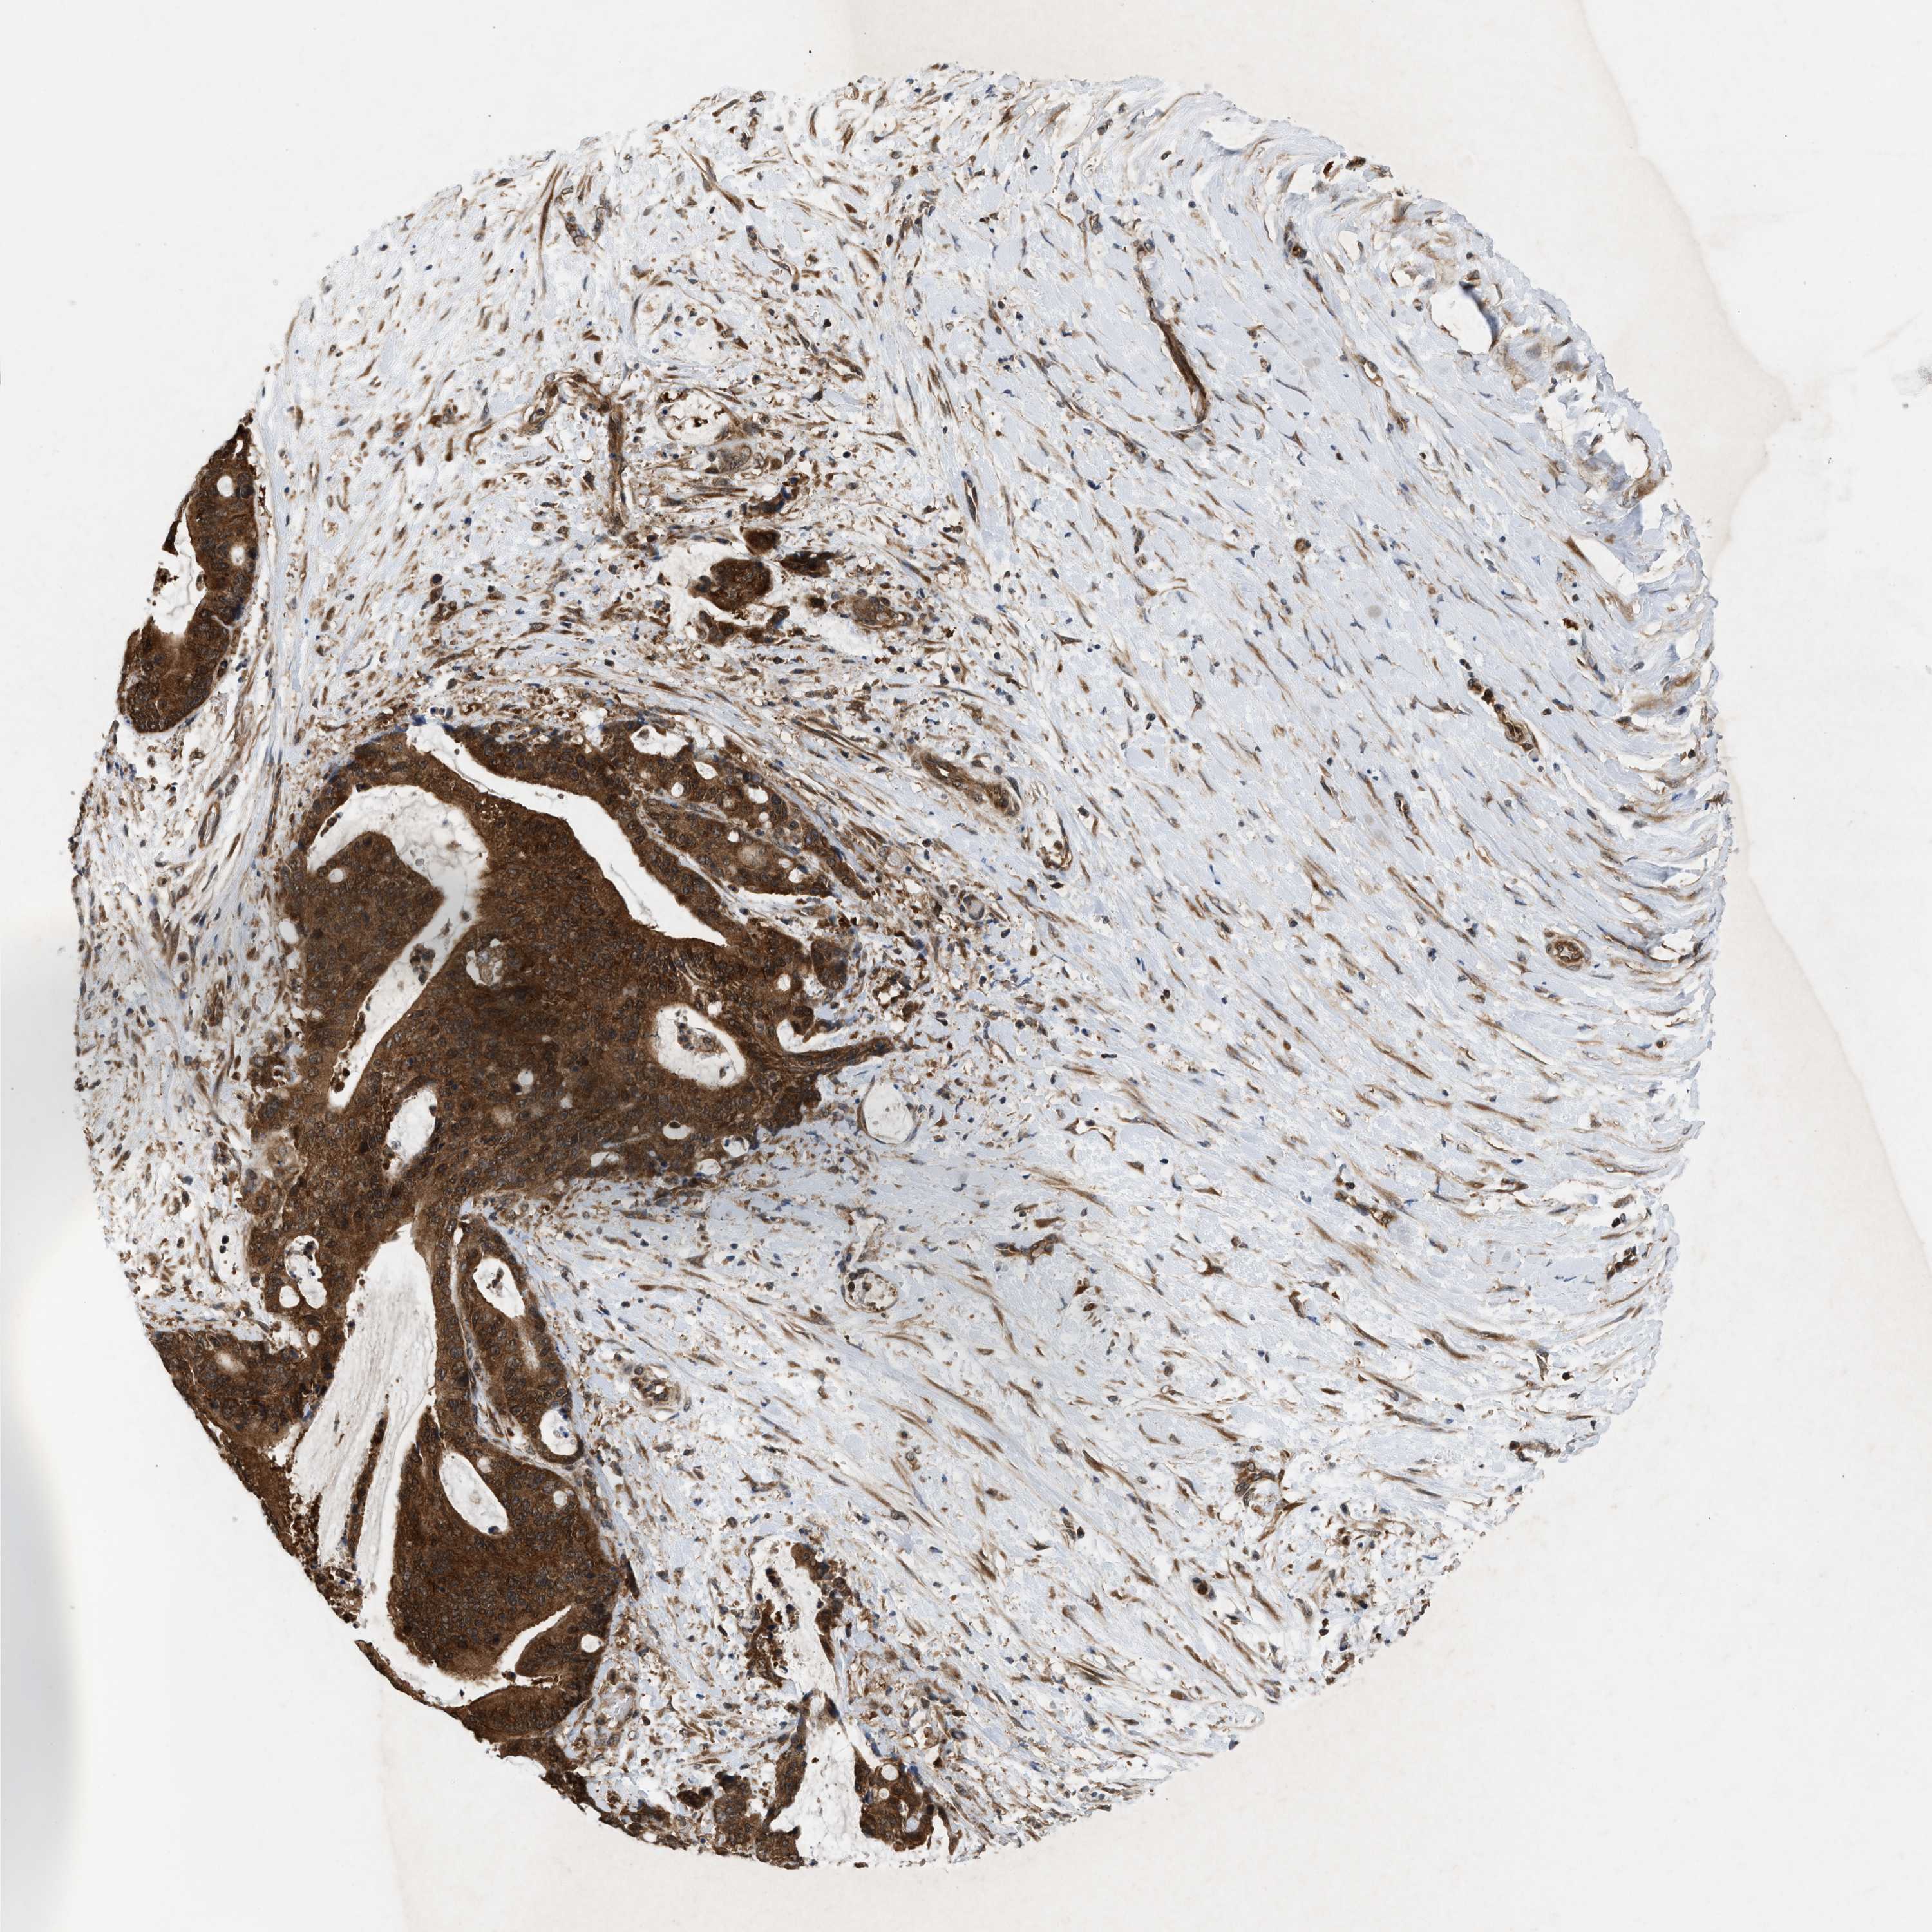

LIVER CANCER - Protein expressioni

A mouse-over function shows sample information and annotation data. Click on an image to view it in a full screen mode. Samples can be filtered based on level of antibody staining by selecting one or several of the following categories: high, medium, low and not detected. The assay and annotation is described here.

Note that samples used for immunohistochemistry by the Human Protein Atlas do not correspond to samples in the TCGA dataset.

Antibody stainingi

Antibody staining in the annotated cell types in the current human tissue is reported as not detected, low, medium, or high, based on conventional immunohistochemistry profiling in selected tissues. This score is based on the combination of the staining intensity and fraction of stained cells.

Each image is clickable and will lead to virtual microscopy that enables deeper exploration of all samples and also displays staining intensity scores, fraction scores and subcellular localization as well as patient and tissue information for each sample.

Antibody HPA008237

Antibody CAB017181

Staining

High

Medium

Low

Not detected

Intensity

Strong

Moderate

Weak

Negative

Quantity

>75%

75%-25%

<25%

None

Location

Nuclear

Cytoplasmic/membranous

Cytoplasmic/membranous,nuclear

Cholangiocarcinoma

Carcinoma, Hepatocellular, NOS